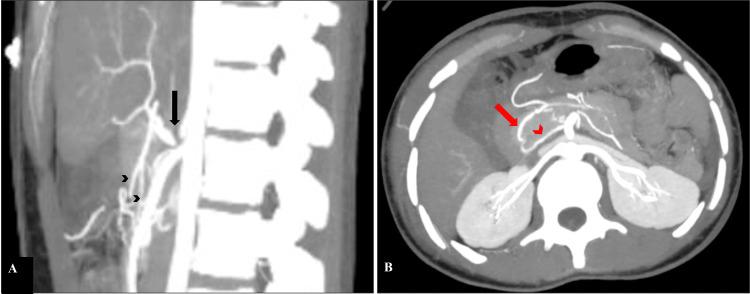

Celiac axis stenosis (CAS) is one of the most prevalent splanchnic arterial pathologies. It seldom results in clinically severe ischemic bowel disease because of the rich collateral circulation from the superior mesenteric artery. Knowledge about the collaterals in celiac artery stenosis guides various interventional procedures. Here, we describe a case of a 19-year-old female with American Association for the Surgery of Trauma (AAST) grade IV splenic injury found to have CAS. Distal splenic artery embolisation was performed via the collateral pathway through the pancreaticoduodenal arcade.

腹腔干狭窄(CAS)是最常见的内脏动脉病变之一。由于肠系膜上动脉丰富的侧支循环,它很少导致临床上严重的缺血性肠病。了解腹腔干狭窄中的侧支循环有助于指导各种介入手术。在此,我们描述了一例19岁女性,其因美国创伤外科协会(AAST)IV级脾损伤而被发现患有CAS。通过胰十二指肠动脉弓的侧支途径进行了脾动脉远端栓塞。